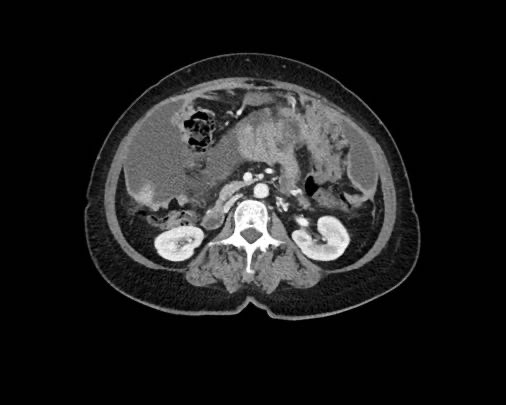

Ca lâm sàng 1

Cuộn qua các lát cắt.

Bạn có thể phát hiện tất cả các tổn thương cấy ghép phúc mạc không?

Bệnh nhân này đã được phẫu thuật và toàn bộ phúc mạc được ghi nhận phủ kín bởi các tổn thương u dạng kê.

Ca lâm sàng 2